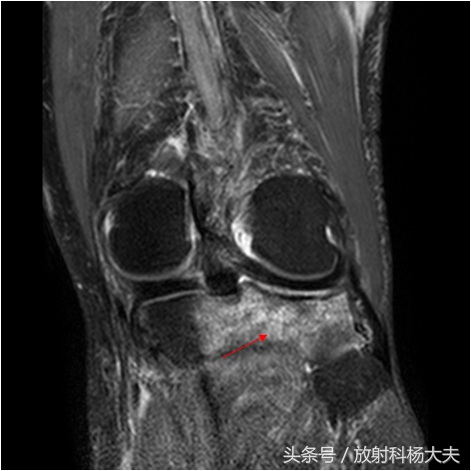

扭伤膝关节,拍片未见异常,做了核磁发现骨挫伤

骨挫伤是外伤所致的骨髓出血、水肿和骨小梁的微骨折, 常见原因是关节囊及韧带的牵拉力、垂直挤压、直接*力暴**、应力损伤、剪切*力暴**等。 只是因为创伤导致的损伤未能引起明显的骨折线,因此在X线平片上看不到骨折而已。骨挫伤还有很多其他名称,比如骨小梁骨折、微骨折等。其基础,不单单是水肿,还有出血和微骨折,由于核磁对水的变化很敏感,因此做核磁是最好的显示骨挫伤的办法。

骨挫伤的形式各异,骨小梁出血灶呈点状、斑片状或散在分布于骨质中。直接*力暴**所致骨挫伤往往造成着力处骨小梁断裂,继而发生广泛渗出,可合并肌腱、关节囊、韧带损伤。撕脱性*力暴**所致骨挫伤可导致肌腱或韧带附着点骨质水肿、出血。应力损伤性骨挫伤特点为:应力作用的方向与骨小梁断裂的方向垂直。剪切损伤特点为骨挫伤的出血点和水肿灶呈斜行,且边界清晰。